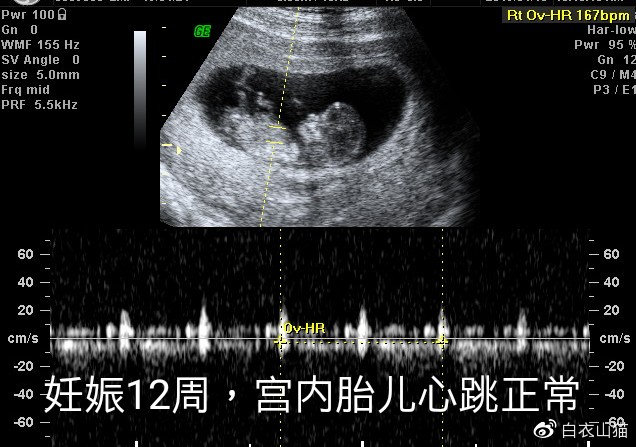

12周,胎儿心跳正常。

小兰到医院后,腹痛开始缓解,不过,医生还是给她做了检查,发现宫内胎儿心跳正常。